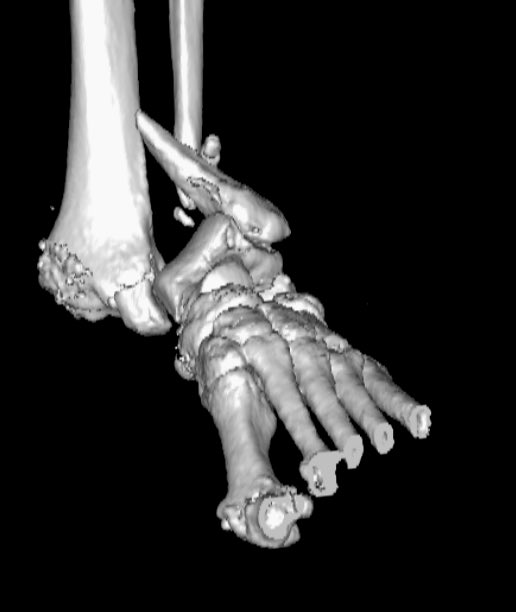

Clinical correlation needed

#exposedfracture#ortho#mskrad#radiologypic.twitter.com/BopZtsmPfI